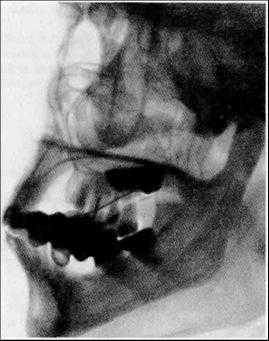

Боковая — взор фиксируется параллельно плоскости и краю стола. На этом снимке мы видим суммарное отображение обеих сторон.

Полуаксиальная (подбородочная) — угол между фронтальной плоскостью и лучом составляет 30°, взгляд фиксируют параллельно столу прямо. Снимок, выполненный в этой проекции (для глаза он является аксиальным), позволяет оценивать глазницы раздельно по всей глубине, что делает его более предпочтительным, особенно при множественных инородных телах.

Критерием качества снимка служит не только четко различимая структура костной ткани, но и наличие мягкотканных ориентиров: контуры глазной щели на прямом снимке, края век и контур переднего отдела глаза на боковом и полуаксиальном. Для получения таких снимков нужно пользоваться лучами средней жесткости.